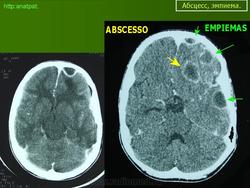

Абсцесс головного мозга – это очаговое скопление гноя в мозговом веществе, окруженное капсулой.

Компьютерная (КТ) или магнитно-резонансная (МРТ) томография головного мозга являются ведущими методами диагностики посттравматических абсцессов, позволяющих судить об их расположении, объеме, структуре, консистенции, содержимом, воздействии на вещество головного мозга. Для исключения опухолей головного мозга, туберкулом, паразитарных заболеваний проводится ОФЭКТ (однофотонная эмиссионная компьютерная томография).